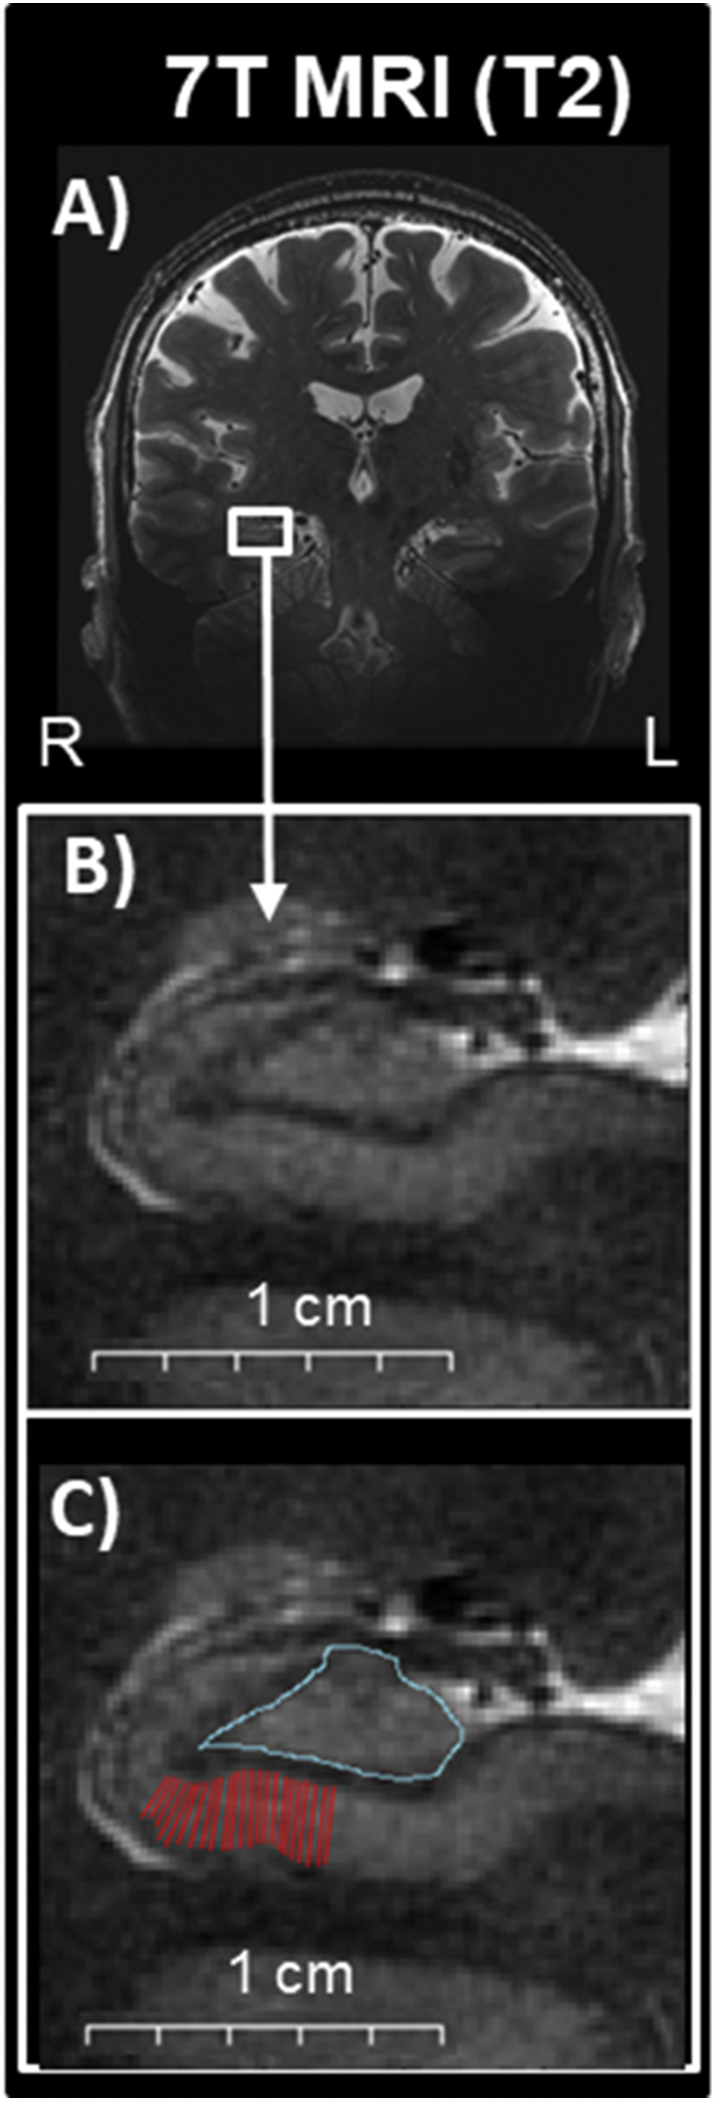

We focused our analysis on the thickness of the CA1 stratum pyramidale (CA1-SP) and stratum radiatum lacunosum moleculare (CA1-SRLM) layers, and the cross-sectional area of the DG/CA3 and the whole hippocampus (Fig. 1). We choose CA1-SP as the primary variable of interest because Lewy-bodies are found in the cell bodies of the CA1 subfield post-mortem (Braak et al., 2006), which has been correlated with pre-mortem memory performance (Adamowicz et al., 2017). We included DG/CA3 as a ‘control’ region because it is relatively spared of Lewy-bodies post-mortem. We included the whole hippocampus for comparison to prior publications. While Lewy-bodies are also prominent in the CA2 subfield at autopsy, this region is not visually discernable even with high-resolution imaging and prior attempts to manually segment CA2 have shown poor inter-study reliability (Yushkevich et al., 2015), therefore we did not include CA2 measures. For all analyses, we separately estimated then averaged the right and left hemispheres. We used raw metrics, rather than adjust for head size, based on our previous data that strongly suggests that these raw measures are likely to reflect the presence of pathology and do not vary with intracranial volume (Kerchner et al., 2010).

Fig. 1.

Hippocampal subfields illustrations on images obtained at 7T MRI. A) Oblique coronal view of a 7T T2-weighted MRI scan. B) Magnified area of the hippocampus where subfields are readily visualized and thus able to be manually traced. C) Superimposed manual tracing of the CA1 (red) and DG/CA3 (turquoise). Abbreviations: R: right, L: left.